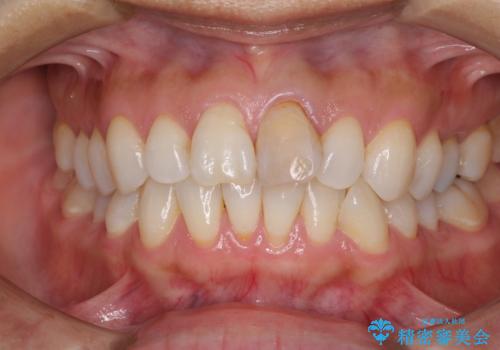

- 10年以上前に神経を取り除いた前歯の変色が気になるとのことで来院された患者様です。

レントゲン写真より、歯根の炎症が認められなかったため、ファイバーコアによる土台築製後、オールセラミッククラウンにて補綴することとしました。

変色とともに、捻れていたことも気になっていたので、その両方を解決させることとしました。

オーダーメイドタイプのクラウンを選択いただいたので、まるで天然の歯と見間違うほど自然に仕上がり、患者様には大変満足していただきました。